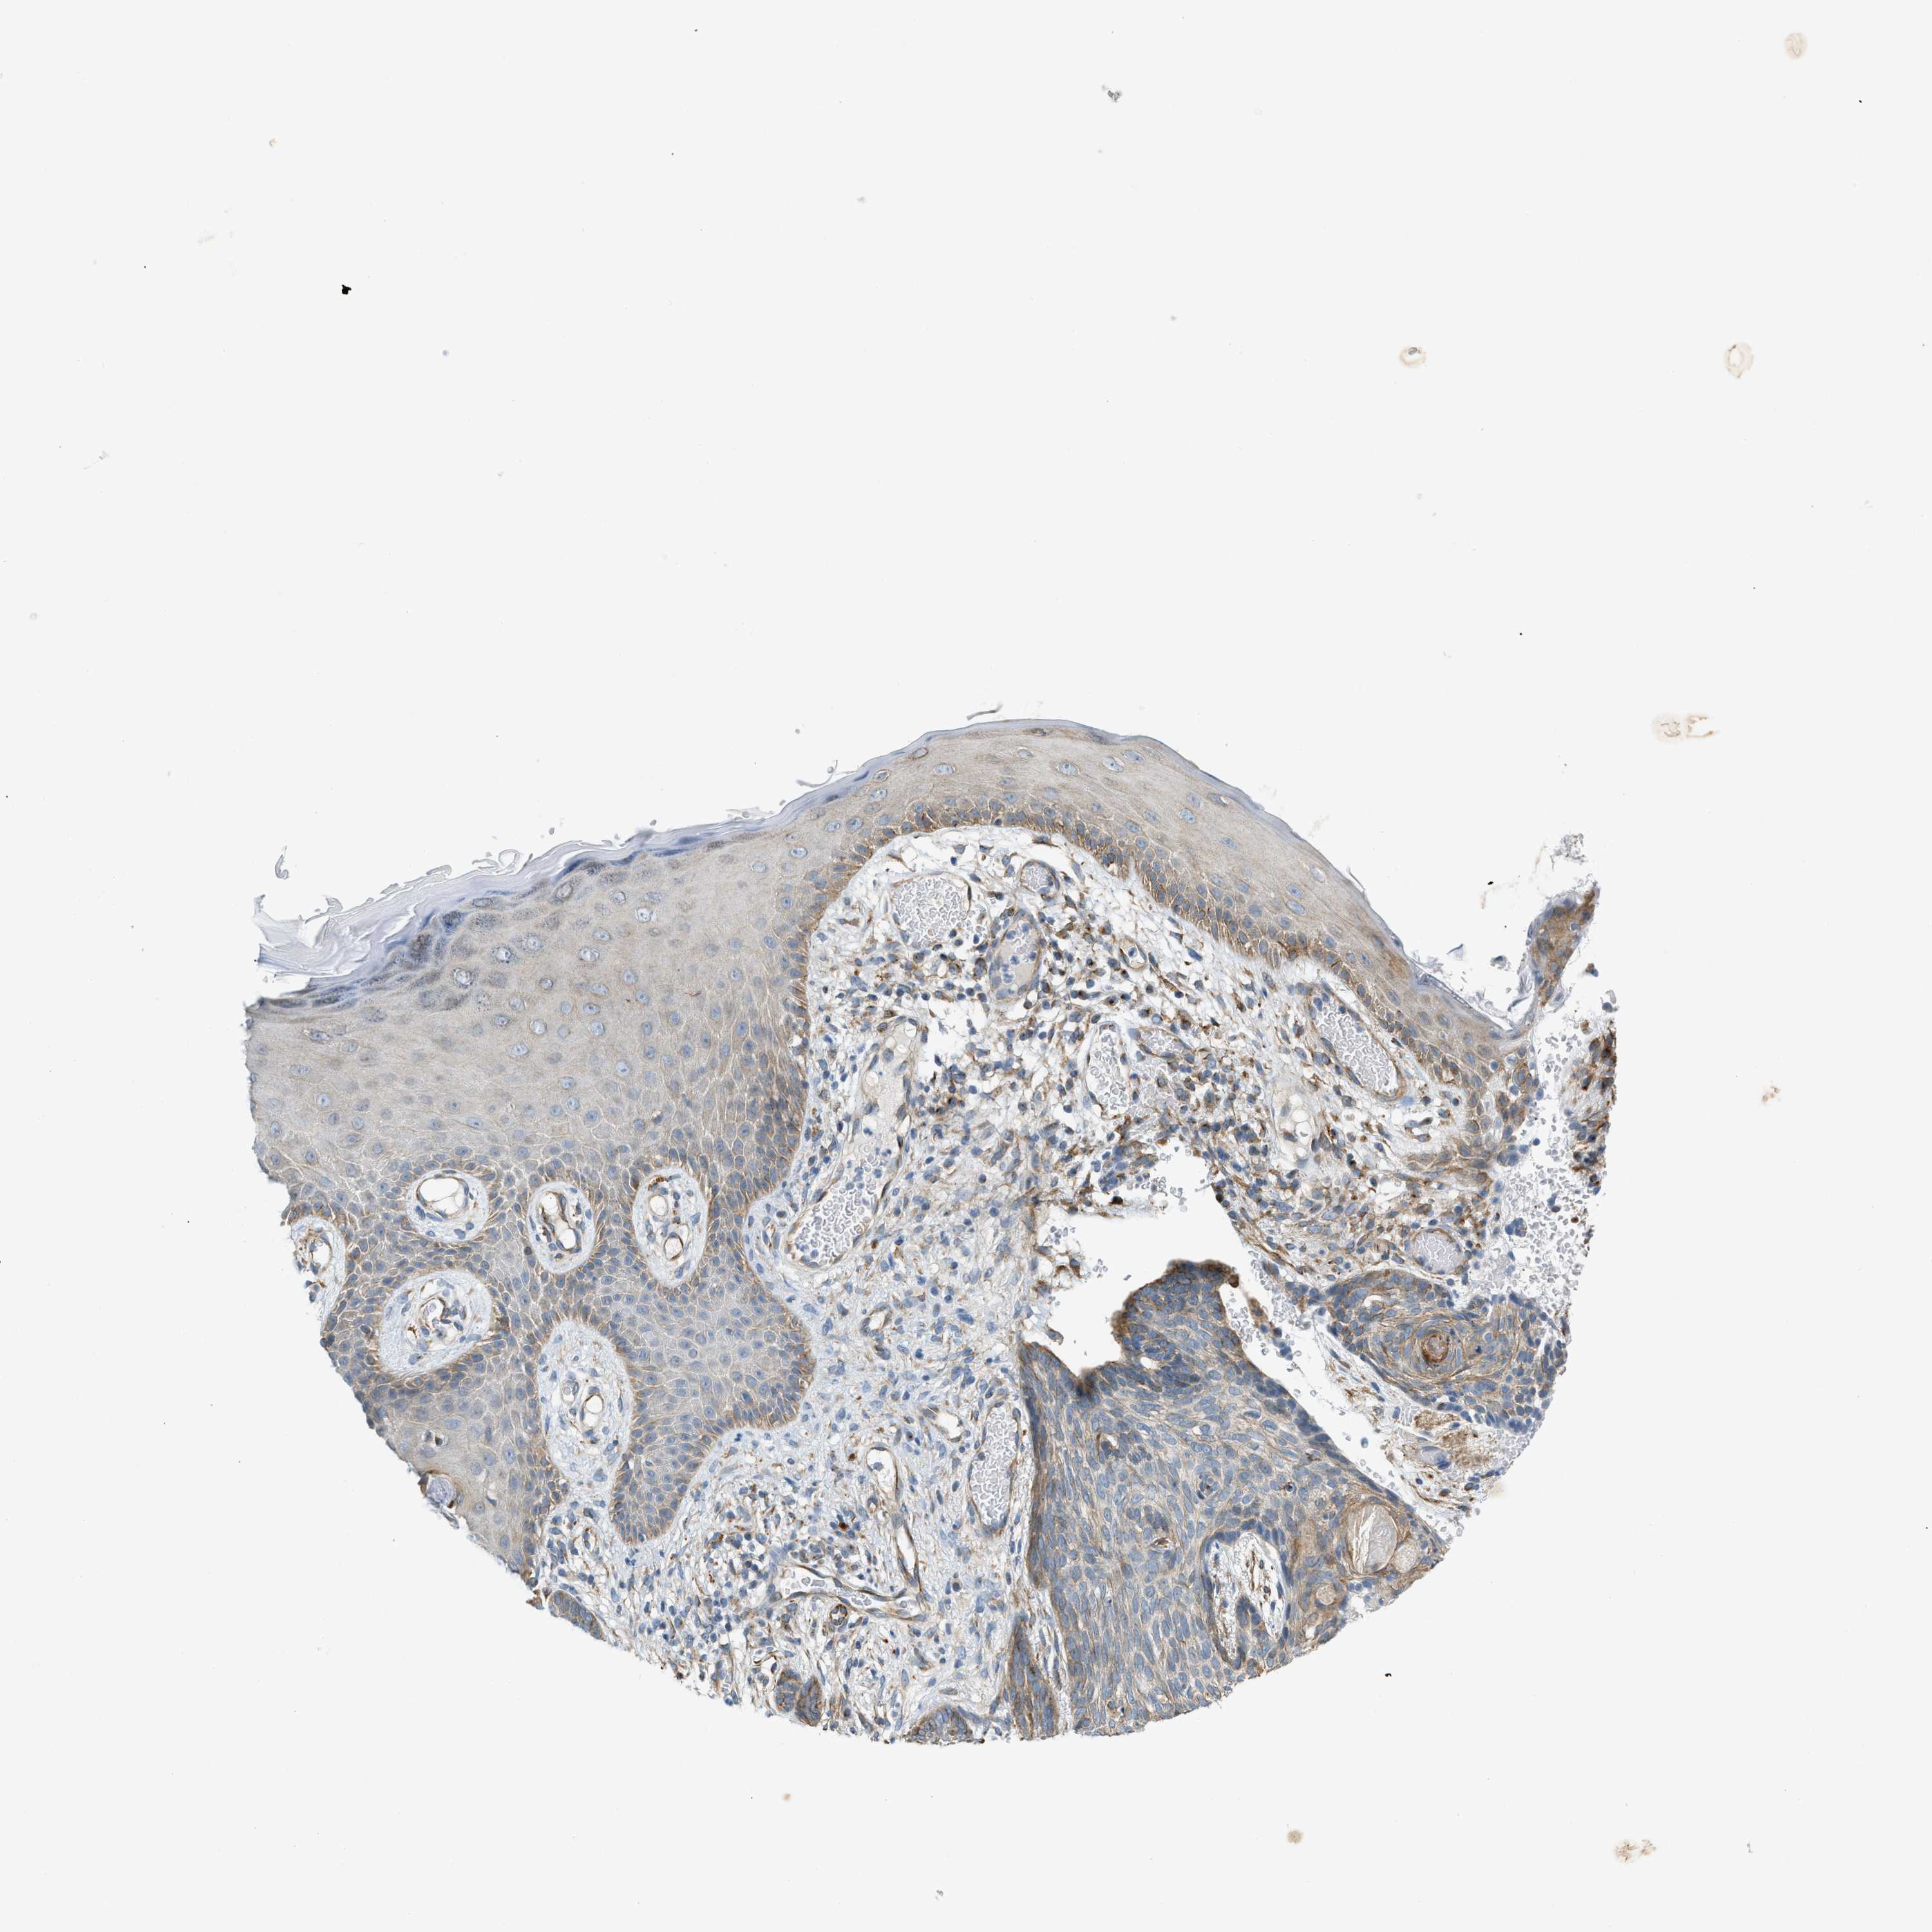

Basal cell and squamous cell cancer

SKIN CANCER - Protein expressioni

A mouse-over function shows sample information and annotation data. Click on an image to view it in a full screen mode. Samples can be filtered based on level of antibody staining by selecting one or several of the following categories: high, medium, low and not detected. The assay and annotation is described here.

Each image is clickable and will lead to virtual microscopy that enables deeper exploration of all samples and also displays staining intensity scores, fraction scores and subcellular localization as well as patient and tissue information for each sample.

Antibody CAB016416

Squamous cell carcinoma, NOS